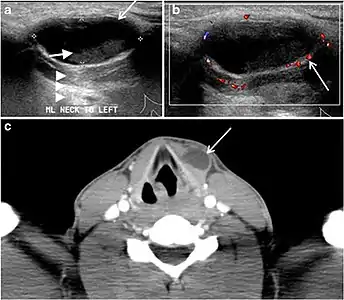

Fig. 4. A 45-year-old male patient presented with anterior mediastinal metastatic PTC lesions and occult primary on imaging. Histopathology examination of the resected thyroid gland revealed micro-foci of PTC; the largest, in the isthmus, measured 4 mm. a transverse greyscale ultrasound of the thyroid demonstrates homogeneous gland with normal echogenicity and size. No focal lesion or micro-calcifications. b Non-enhanced CT scan obtained as part of PET/CT examination shows a heterogeneous, large, relatively dense anterior mediastinal mass (white arrow) with peripheral calcification (arrowheads). Thyroid gland has normal CT appearance with no abnormal FDG uptake (not shown).[1]

Fig. 7. A 51-year-old female patient post total thyroidectomy for PTC with elevated thyroglobulin measurement. an Axial non-enhanced CT scan of the neck at the level of the thyroid bed demonstrates a well-defined, rounded, homogenously dense soft tissue situated between the trachea and left internal jugular vein (white arrow). b Transverse ultrasound image of the neck demonstrates a well-defined, homogeneous, hypoechoic soft tissue nodule measuring 6 mm (white arrow) with no detected micro-calcifications. Biopsy showed a predominantly residual normal thyroid tissue with micro-foci of PTC.[1]

Fig. 8. A 48-year-old male patient post total thyroidectomy with PTC recurrence. a Transverse greyscale ultrasound of the neck demonstrates a left thyroid bed heterogeneous, predominantly hypoechoic irregular lesion with calcifications (white arrow). b A spot image of iodine 123 total body scan of the neck demonstrate a focus of abnormal radiotracer uptake at the left thyroid bed (Black arrows) between the annotated markers. c Enhanced axial CT scan of the neck demonstrates an enhancing large left thyroid bed mass (white arrow) with no calcifications. The lesion exerts a mass effect on the oesophagus (black arrow) and is inseparable from the trachea.[1]